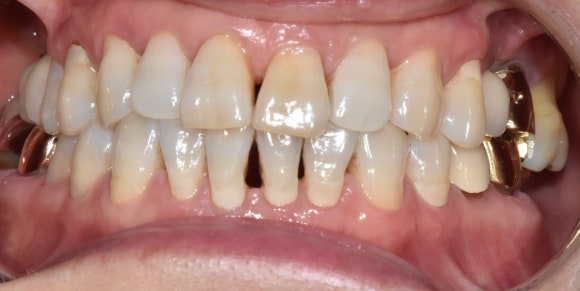

첫번째 케이스

서울재생치과에서 진행한 케이스를 소개드리겠습니다.

오른쪽 앞니를 주의해서 관찰해주세요.

오랜기간 치수괴사를 겪으면서 짙은 오렌지색으로 변색이 일어난 경우에 해당됩니다.

신경치료 후 미백제를 넣고 3회 차에 미백치료를 종료하셨습니다.

(색상 회복이 굉장히 빠르셔서, 몇 번 더 진행하면 옆의 자연치보다 더 하얘질 것 같았습니다^^;)

치료 전 후